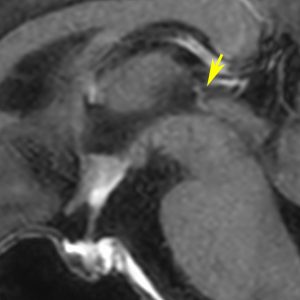

再発ジャーミノーマの画像です。延髄背側の閂 ovexという部位に再発しています。

このパターンはとても多いです。なぜかというと,全脳室照射の時に,第4脳室下端のovexの上衣 ependyum を照射野に入れない放射線治療医の先生がいるからです。放射線科の先生にもちょっとした知識が必要なのです。

これは再治療で腫瘍が消えても不可逆的な重症の延髄障害を残してしまいます。